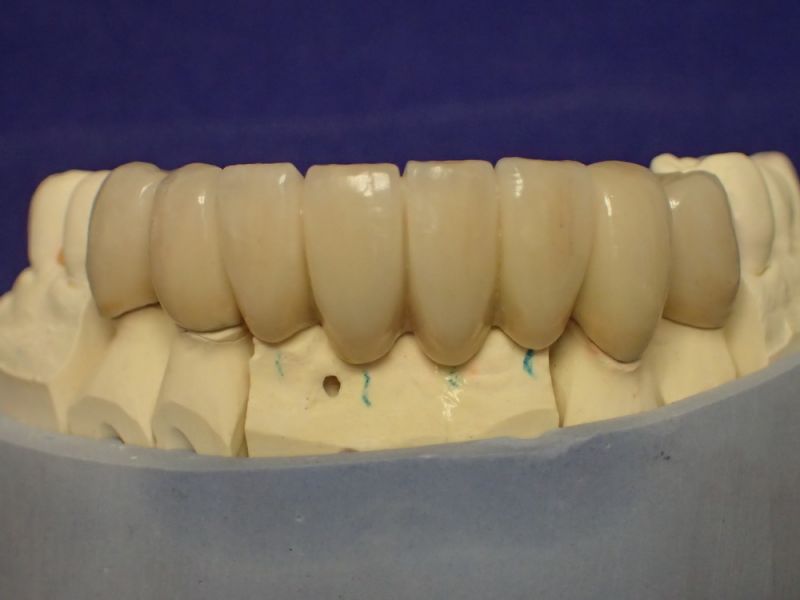

Langjährige Kieler Patientin erhält neue Unterkieferfrontzahnbrücke

Ein bißchen hats gedauer, dafür ist die Patienitn mit dem Ergebnis umso zufriedener.

Die Oberkieferteleskoparbeit hat die Patientin inzwischen fast 25 Jahre im Mund und die Unterkieferfronzahnbrücke könnte das ebenfalls erreichen.